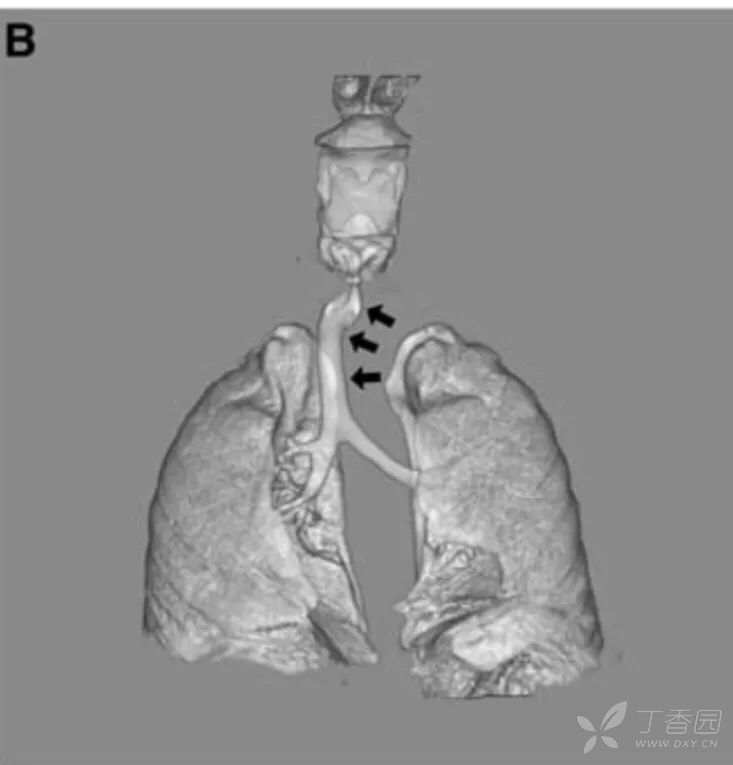

因怀疑胸腔内肿物而进行胸部CT检查,显示气管有右偏(图,B,箭头所示),但没有发现肿物或血管压迫。患儿在影像检查时哭吵。

考虑到这一发现和胸部CT显示没有胸腔内异常,结论是,这种气管弯曲并不提示存在病变,而且与患儿的急性喉炎无关。